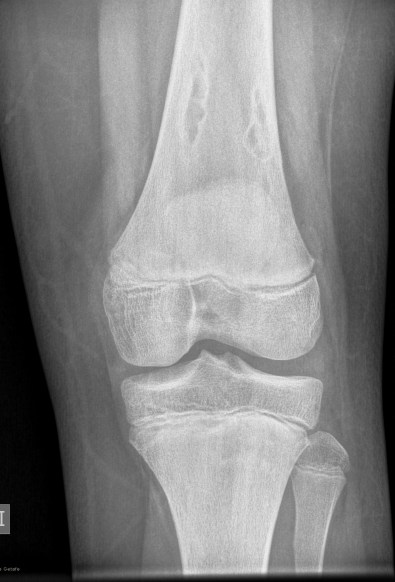

Cuando terminé la exploración y el radiólogo la chequeó le pidió al paciente unas placas para demostrar estos hallazgos, el resultado de las radiografías son estos, se aprecia perfectamente en la lateral los cambios o hallazgos que mostraba la ecografía MSK, mira:

Observa como en la espina tibial anterior, parece que el hueso se está despegando.

Como conclusión, podemos decir, una vez tenemos las imágenes de ambas técnicas que el diagnóstico de estos hallazgos radio-ultrasonográficos es la existencia de irregularidad a nivel de la tuberosidad tibial izquierda con engrosamiento de la porción insercional del rotuliano y cambios inflamatorios en partes blandas adyacentes.

Hallazgos que junto con los visualizados en RX son compatibles con enfermedad de Osgood-Schlatter.